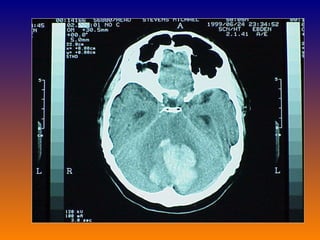

Subarachnoid hemorrhage CT scan: Small bleed may be missed in CT (10%) After 7 days CT may be normal in 50% cases CSF examined if CT normal it should not precede CT Lumber puncture: opening pressure high Definitive: RBC >100,000/cmm Xanthochromia-develops in 1-2 days MRI sensitive for bleed >10 days old useless for acute investigation

Subarachnoid hemorrhage CTscan: Small bleed may be missed in CT (10%) After 7 days CT may be normal in 50% cases CSF examined if CT normal it should not precede CT Lumber puncture: opening pressure high Definitive: RBC >100,000/cmm Xanthochromia-develops in 1-2 days MRI sensitive for bleed >10 days old useless for acute investigation